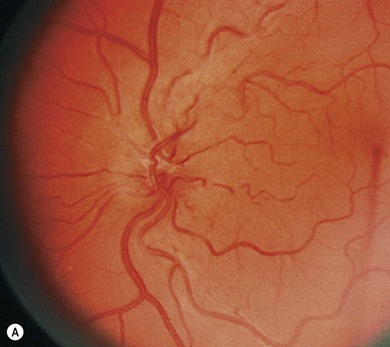

Two categories of dilated fundoscopic exam findings in optic neuritis

Papillitis

“Macular star”

Associated with papillitis in cases of neuroretinitis

Suggests an infectious etiology, such as viral, toxoplasma, bartonella, Lyme, and syphilis

Looks more like a firework to me

Retrobulbar neuritis